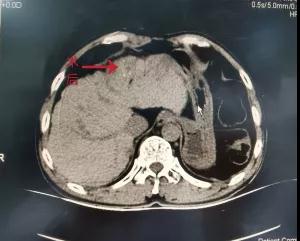

血管病介入科主任邓有峰立即组织科室成员进行病例讨论,在充分评估患者目前情况及手术风险后决定对患者行肝癌微波消融术。2020年12月02日在放射科积极配合下行CT引导下肝癌微波消融术。常规消毒铺巾、局部麻醉后,将微波消融穿刺针在术前体表定位处逐层插入肝脏肿瘤瘤体内,经过约10分钟70℃消融治疗再次行CT显示原肝脏肿瘤部位出现气化现象可见多个小空洞,周围呈磨玻璃样改变。手术过程顺利,患者无特殊不适。术后第二天复查血常规、肝功无明显异常,患者出院。